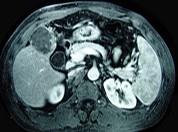

问题 男性,60岁,右上腹胀不适,右肝区叩击痛,影像检查如图,最可能的诊断是 ( )

选项 A.肝硬化 B.肝硬化、再生性肝癌 C.肝硬化、腹腔间质瘤 D.肝硬化、膈下脓肿 E.肝硬化、结节性增生

答案 B